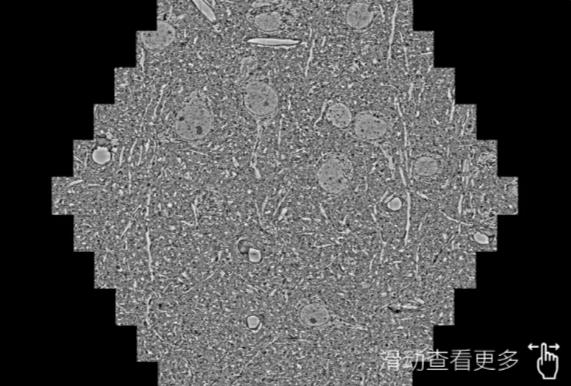

鼠脑切片。左图使用青岛蔡司青岛扫描电镜MultiSEM706对165μmx143pm面积区域成像,耗时仅需1.5秒。右图为鼠脑切片中30μm区域放大效果。样品由芝加哥大学B.Kasthuri提供。

使用蔡司高速青岛扫描电镜MultiSEM对1mm²人脑皮层组织进行高分辨成像,并对其中的各种细胞结构进行三维重构分析。左图展示了2x3mm²组织平面中锥体神经元的三维重构效果。右图显示了局部体积神经元三维重构。图像由哈佛大学chtman实验室提供,渲染图由D. Berger 制作。